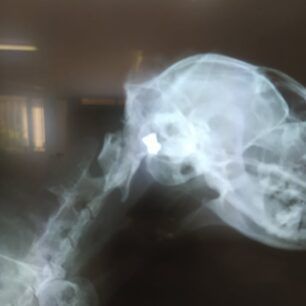

Η ακτινογραφία ήταν για άλλη μια φορά η εξέταση που έδωσε την απάντηση στο γιατί μια γάτα που ζούσε στην πόλη της Λαμίας στη Φθιώτιδα στη διασταύρωση των οδών Κύπρου και Ασωπού, υποφέρει. Το σφαιρίδιο του αεροβόλου με το οποίο κάποιος είχε πυροβολήσει το ζώο ήταν καρφωμένο κοντά στο αριστερό αυτί της.

Ο γιατρός συνέστησε ακτινογραφία ώστε να φανεί πόσο μεγάλο ήταν το πρόβλημα στο αυτί του, μιας και φαινόταν ότι το πρόβλημα εκεί υπήρχε, αφού είχε διαταραχθεί το αίσθημα της ισορροπίας του γάτου… Και να σήμερα το αποτέλεσμα!

Δεν ήταν αποτέλεσμα γατοκαυγά ή ίωσης, αλλά  πυροβολισμός από αεροβόλο! Ναι πολύ σωστά! Κάποιος στη γειτονιά πυροβόλησε στο κεφάλι το γάτο! Τον ενόχλησε το νιαούρισμά του, ή απλά και μόνο η ύπαρξή του;

Ο Ρούμπη σήμερα εγχειρίστηκε σε ιδιωτικό κτηνιατρείο και μετά την αφαίρεση του βλήματος από το κεφαλάκι του παραμένει εκεί  με ορούς και θεραπείες. Η αγωνία μας είναι μεγάλη για το ποια θα είναι η εξέλιξη της υγείας του. Ευχόμαστε και ελπίζουμε να πάνε όλα καλά.